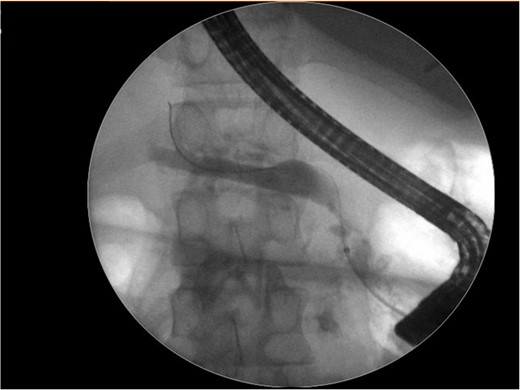

An abdominal ultrasound (Fig. 1), a computed tomography (Fig. 2) and a magnetic resonance cholangiopancreatography (MRCP) resonance showed diffuse dilation of the main pancreatic duct the duct of Santorini and the secondary ducts. Stones inside the main pancreatic duct in the head region, measuring approximately 1.1 cm. Reduction in the thickness of the pancreatic parenchyma, associated with small calcifications in between (Fig. 2).

Abdominal ultrasound shows a diffuse dilation of the main pancreatic duct.